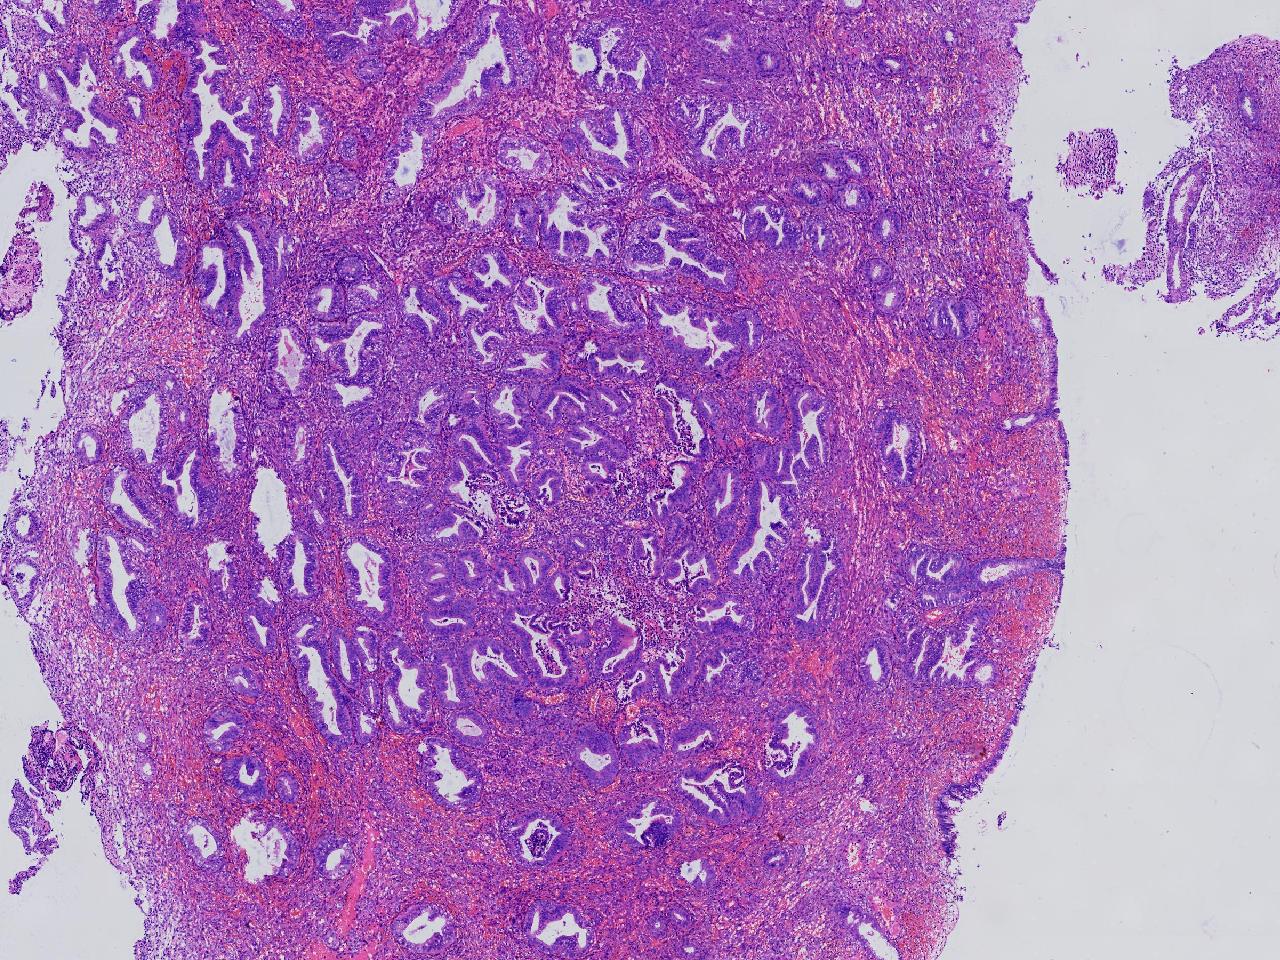

请教。1.有没有非典? 2.内膜是什么变化?

女,50岁,彩超示:粘膜厚度1.1cm。宫腔可见数个高回声,提示宫腔息肉。

子宫内膜+内膜息肉

灰粉色不整形软组织多块,3X3X2厘米。

子宫内膜息肉。

没有非典。

无非典型性子宫内膜增生,子宫内膜息肉

无非典内膜伴息肉。